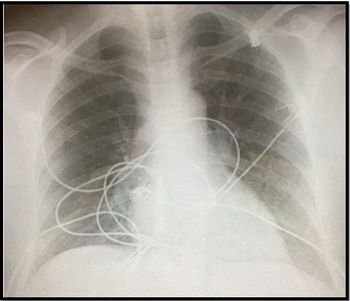

The 32-year-old presents to the ED after 2 hours of acute nonpleuritic dyspnea--a first-ever episode. How would you proceed?